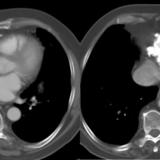

Peric recesses

Date: 01/26/2009

Views: 4437